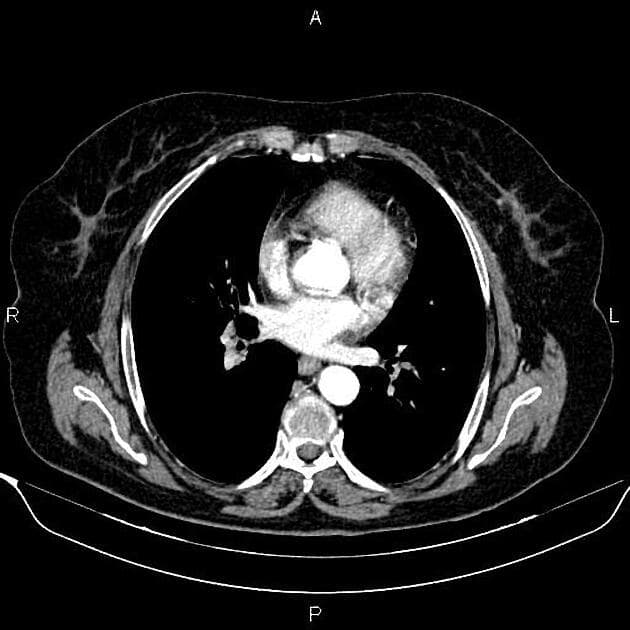

- Một khối nang khu trú một phần lồi ra ngoài (exophytic) kích thước 48 mm, thành dày ngấm thuốc (enhancement) và có các vách ngăn cùng các nốt ngấm thuốc lệch tâm (eccentric enhancing nodules) được ghi nhận ở phần giữa của thận phải.

- Một vài mạch máu tuần hoàn bàng hệ (collateral circulation) nhỏ giãn được ghi nhận trong khoảng gian thận (perinephric space).

Khối nang thận - phân loại Bosniak IV (Renal cystic mass - Bosniak class IV)

- "Các khối nang thận phân loại Bosniak IV có nguy cơ ác tính từ 70-90% và thường là ung thư biểu mô tế bào thận dạng nang."

- "Các đặc điểm hình ảnh chính bao gồm thành dày ngấm thuốc, vách ngăn ngấm thuốc và các nốt ngấm thuốc lệch tâm."

- "Phẫu thuật cắt bỏ (cắt thận bán phần hoặc toàn phần) là phương pháp điều trị tiêu chuẩn cho tổn thương Bosniak IV."